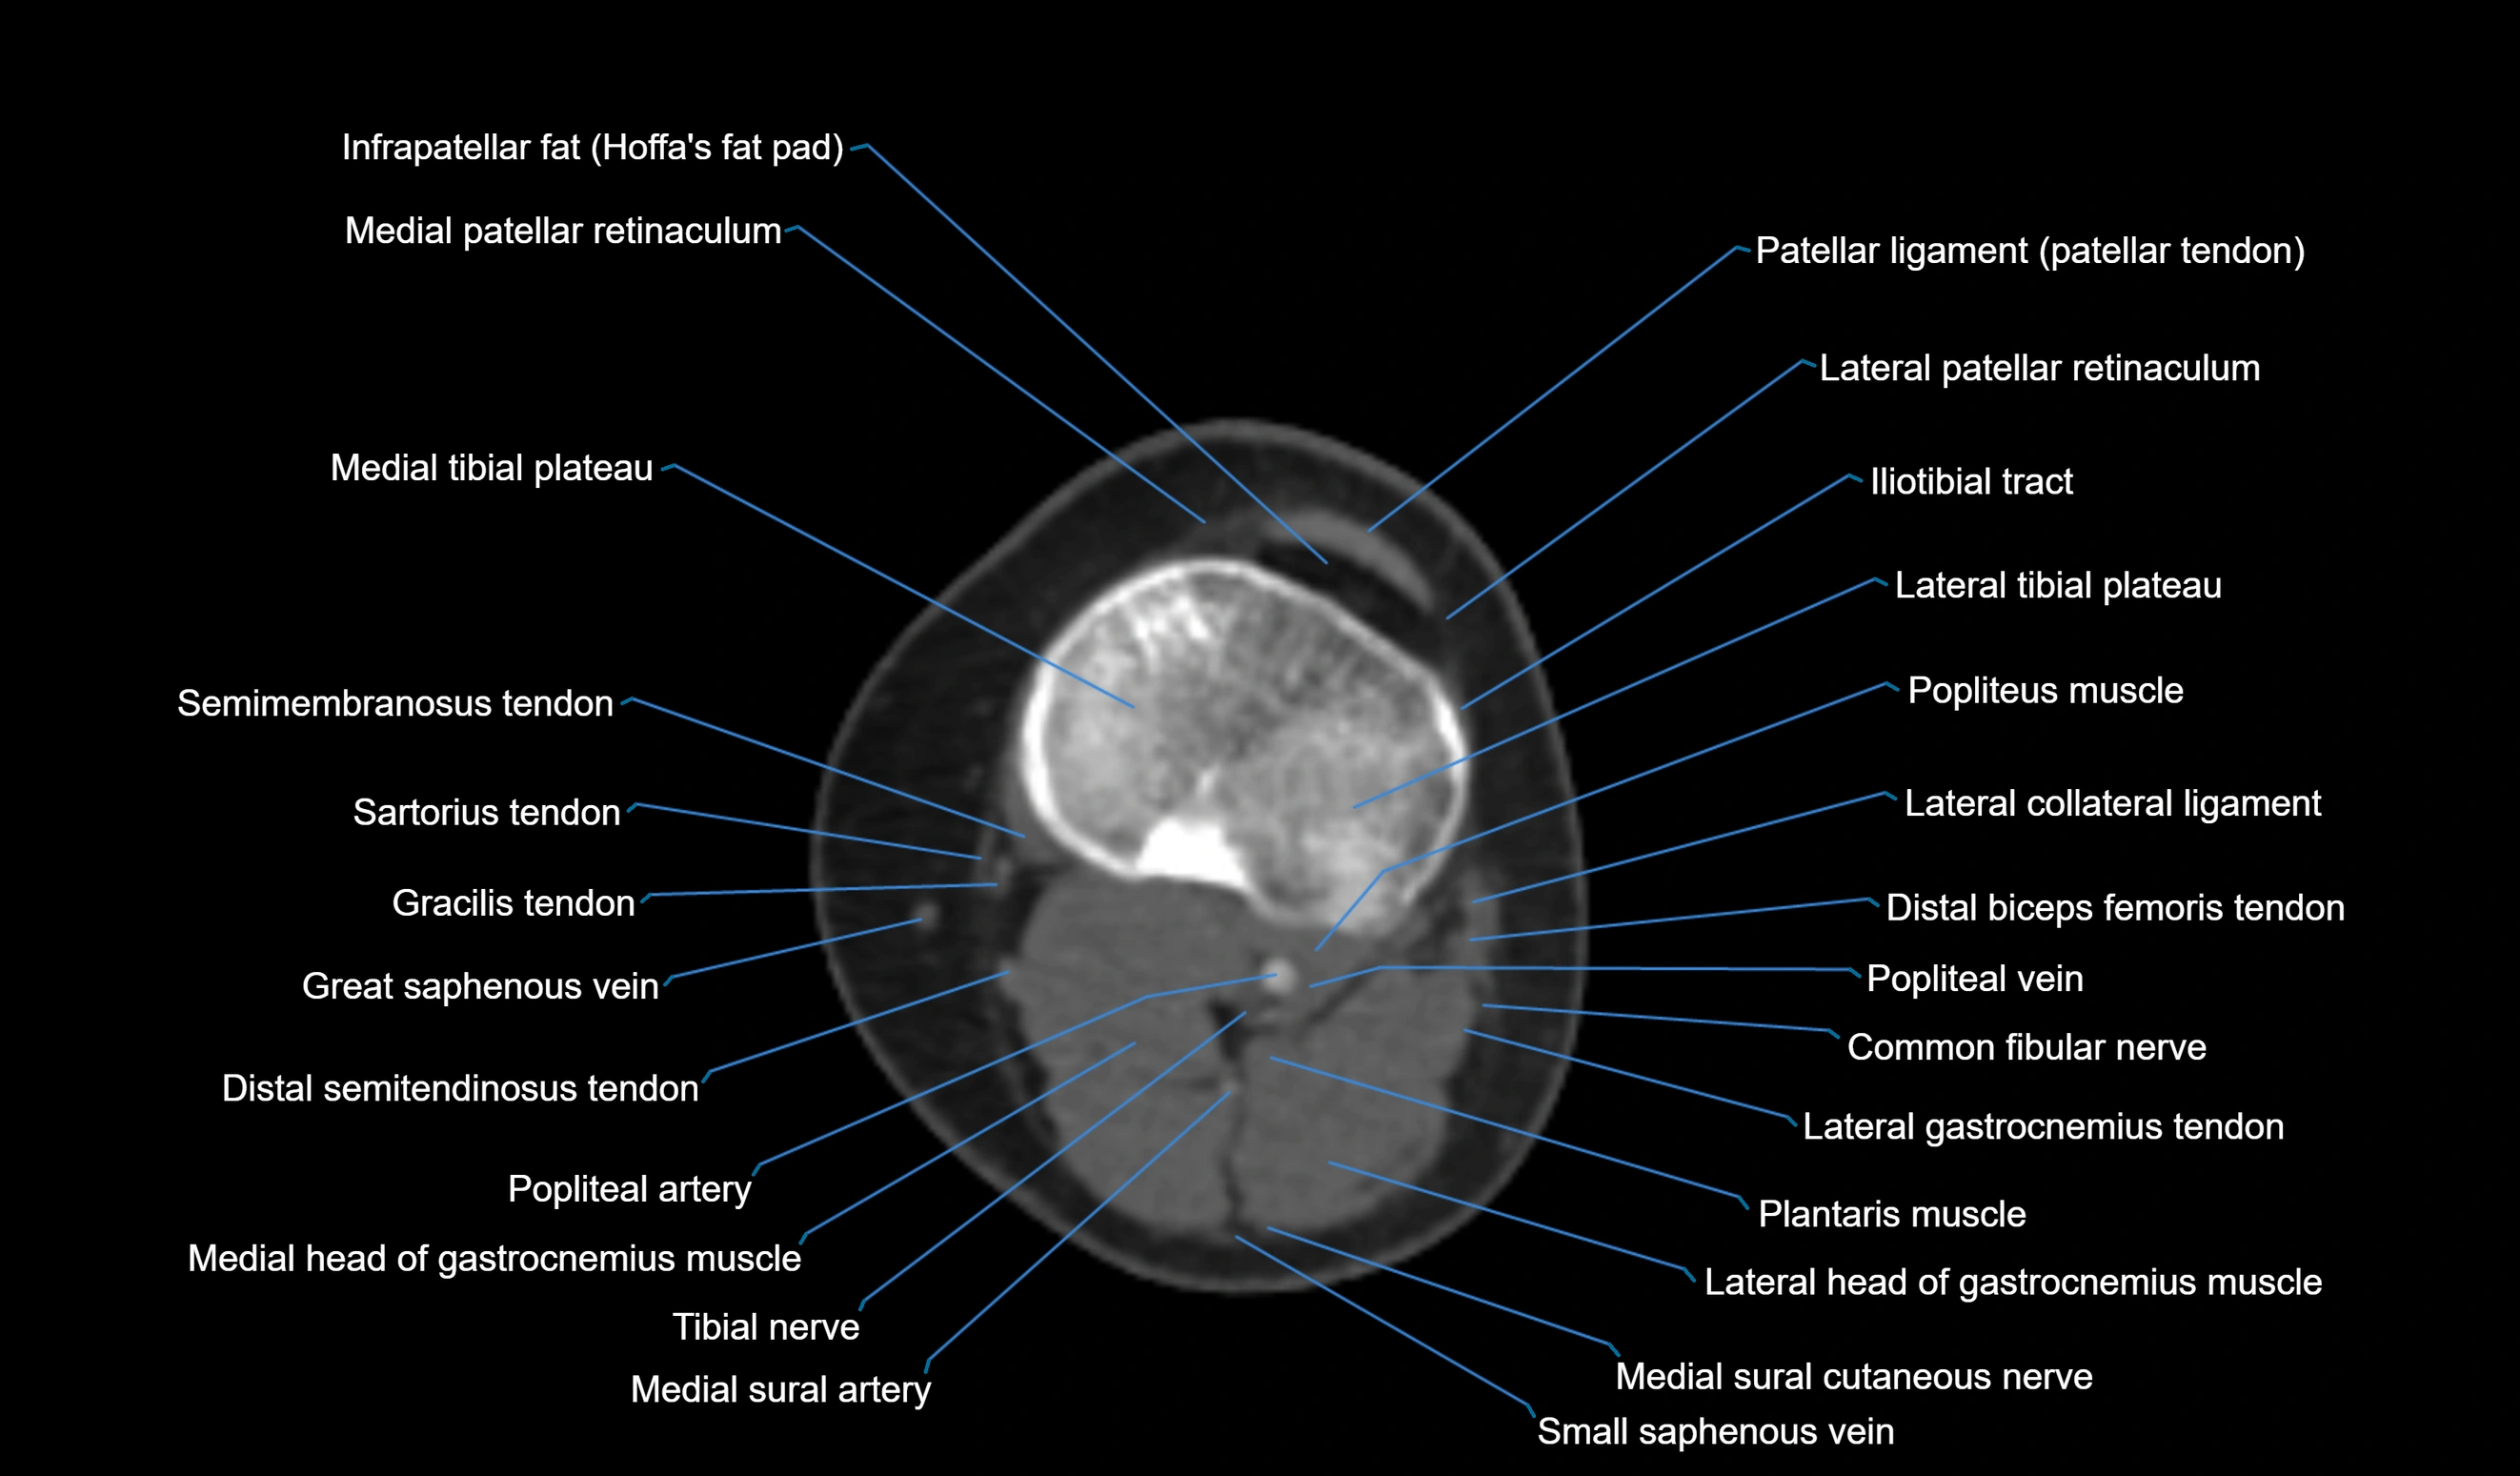

- Common fibular nerve

- Lateral collateral ligament

- Lateral gastrocnemius tendon

- Lateral head of gastrocnemius muscle

- Lateral tibial plateau

- Medial collateral ligament

- Medial head of gastrocnemius muscle

- Medial patellar retinaculum

- Medial sural cutaneous nerve

- Medial tibial plateau

- Patellar tendon (patellar ligament)

- Popliteal artery

- Popliteal vein

- Popliteus muscle

- Small saphenous vein

- Tibial nerve